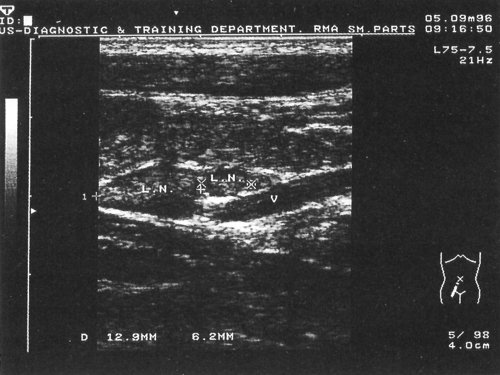

Рис. 2. Эхограмма с изображением измененных лимфатических узлов на фоне доброкачественного лимфаденита в подвздошной области при иерсиниозе. Использован датчик с частотой 5,0 МГц.

Рис. 3 . Эхограмма с изображением доброкачественного лимфаденита в парааортальной области (слева) и в подвздошной области (справа) на фоне иерсиниоза. Использован датчик с частотой 5,0 МГц.

Рис. 4. Эхограмма с изображением доброкачественного лимфаденита в подвздошной области на фоне иерсиниоза. При этом удается хорошо различать составные части лимфатического узла. Использован датчик с частотой 5,0 МГц.

При ультразвуковом исследовании у всех пациентов с клиникой острого аппендицита (32 человека) не было выявлено изменений, ни в стенке червеобразного отростка ни в стенке терминального отдела подвздошной кишки. У всех пациентов при исследовании датчиком 3,5 МГц в правой подвздошной области визуализировались расположенные в виде "цепочки" увеличенные лимфатические узлы. Чаще лимфатические узлы были множественные, они никогда не имели тенденции к слиянию. Максимальный горизонтальный диаметр составлял 10,0 - 15,0 мм. При этом соотношение длинной и короткой осей узла составляло в среднем 2,1 (от 1,7 до 2,7). Форма большинства узлов была овальной. Лимфатические узлы визуализировались как гипоэхогенные образования. При размерах узла более 10,0 мм удавалось дифференцировать его центральную часть повышенной эхогенности. Лимфатические узлы меньших размеров визуализировались в виде единой солидной гипоэхогенной структуры без дифференциации на составные части.

У части больных при проведении дополнительного обследования датчиком 5,0 МГц удавалось визуализировать невидимые при использовании датчика 3,5 МГц лимфатические узлы размерами от 5,0 до 8,0 мм. При этом в единичных случаях удавалось визуализировать составные части этих не увеличенных лимфатических узлов. Сердцевина определялась в виде деформированной (суженной) линейной структуры более высокой эхогенности, корковая часть была гипоэхогенной, широкой. Практически во всех случаях применения датчика с частотой 5,0 МГц в дополнение к датчику 3,5 МГц удавалось выявлять утолщение стенки терминальной части тонкого кишечника.